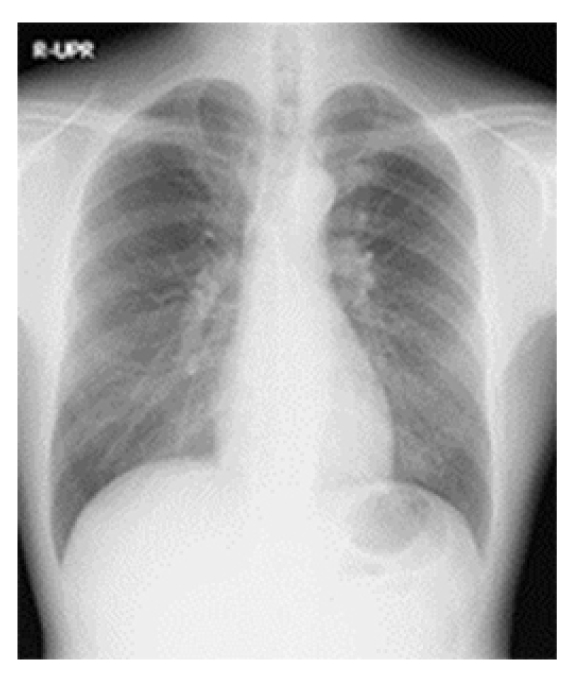

単純X線撮影